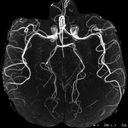

res-4-vascular-brain.jpg